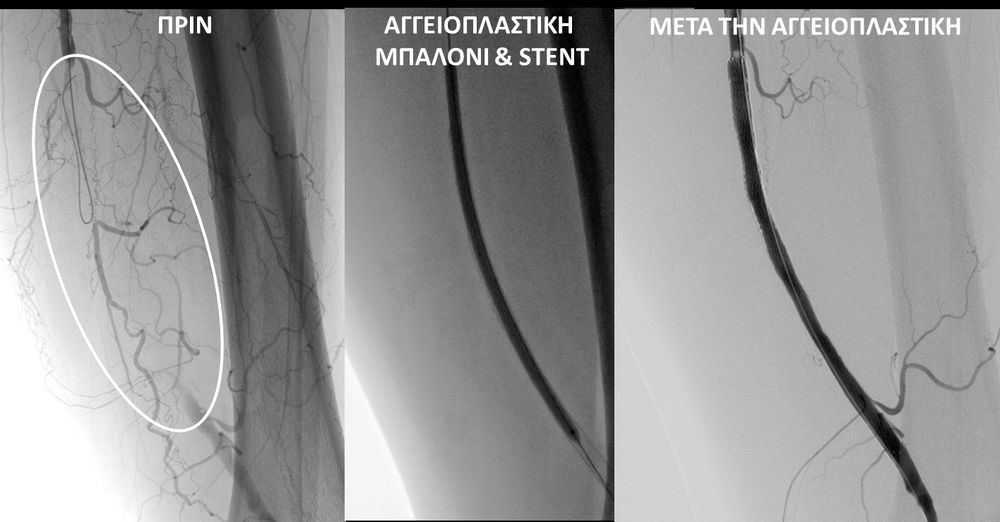

O σακχαρώδης διαβήτης είναι μεταβολική ασθένεια η οποία χαρακτηρίζεται από αύξηση της συγκέντρωσης του σακχάρου στο αίμα (υπεργλυκαιμία) και διαταραχή του μεταβολισμού της γλυκόζης. Ο βαθμός αύξησης της γλυκόζης στο αίμα και η παραμονή των αυξημένων τιμών της για μεγάλο χρονικό διάστημα βλάπτουν, κυρίως, τα μικρά αγγεία, προκαλώντας διαβητική νευροπάθεια, διαβητική νεφροπάθεια, αμφιβληστροειδοπάθεια κ.τ.λ., με σοβαρότατες συνέπειες σε πολλά όργανα-συστήματα.Στην Ελλάδα κάθε χρόνο πραγματοποιούνται 2.000 – 3.000 ακρωτηριασμοί κάτω άκρων, αφού το 4-5% των πασχόντων από διαβήτη εμφανίζει περιφερική αγγειοπάθεια με έλκη ή και γάγγραινα στα πόδια. Σε ποσοστό 80% οι ακρωτηριασμοί θα μπορούσαν να αποφευχθούν και η επεμβατική ακτινολογία μπορεί να βοηθήσει σημαντικά.Η διαδερμική ενδαγγειακή αγγειοπλαστική (percutaneous transluminal angioplasty, PTA) είναι μια ελάχιστα επεμβατική μέθοδος αντιμετώπισης των αρτηριακών στενώσεων ή και αποφράξεων του διαβητικού ποδιού (περιφερικήδιαβητικήαρτηριοπάθεια).